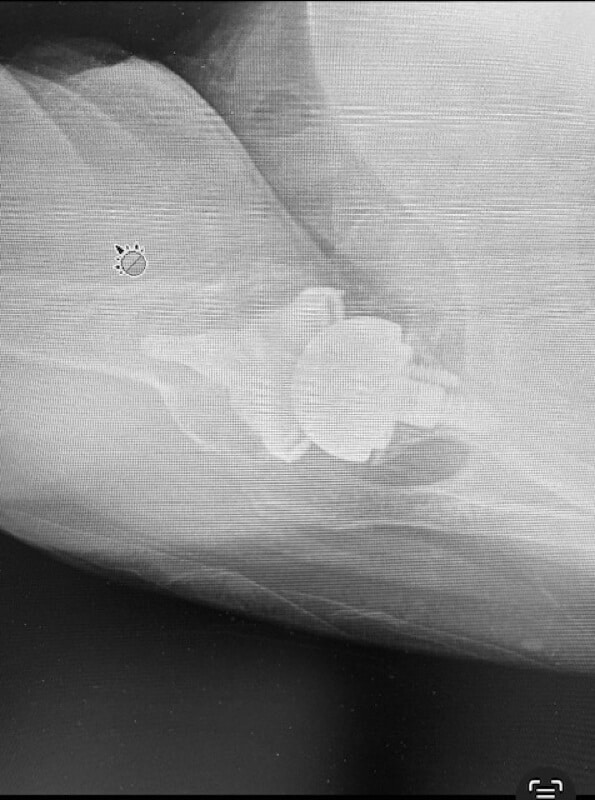

Shoulder Innovations, InSet